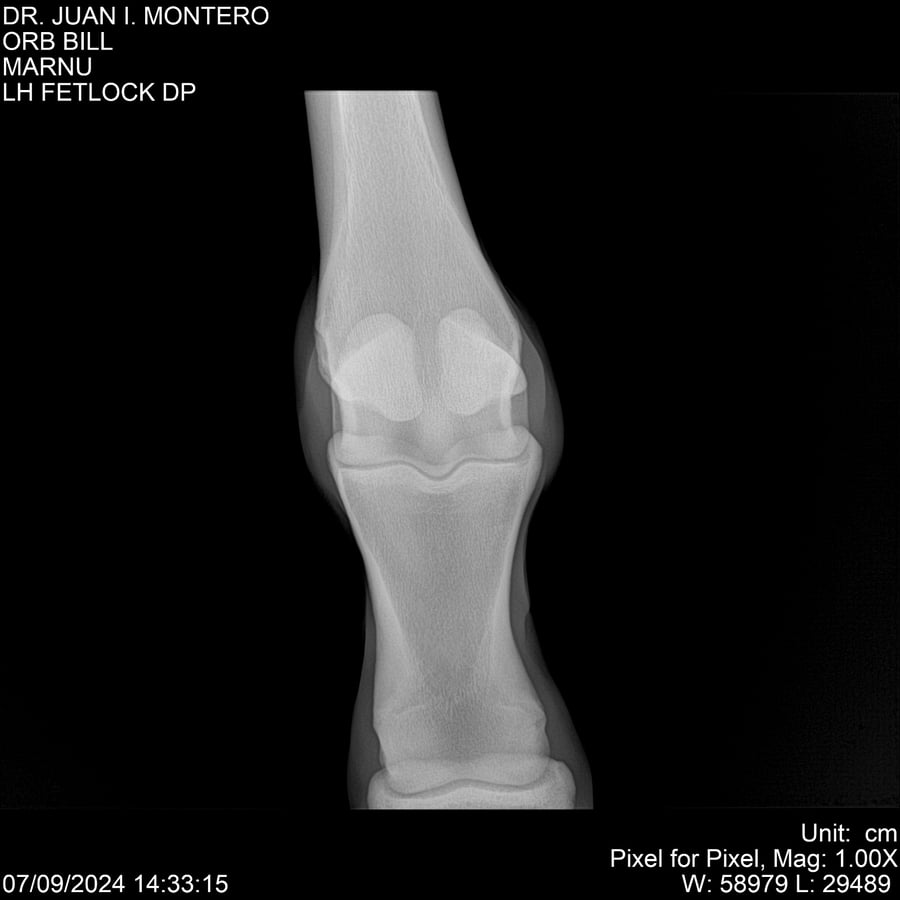

LOTE 7, ORB BILL 🔥 🔥 🔥 Lote Anterior Volver al remate Lote Siguiente Ficha Contacto Montevideo - Ficha del Lote Identificador: #282523 Categoría: Yeguarizos Montevideo - 83 Visualizaciones ClicData Contacto Empresa: Abelenda N. R., Walter Hugo Nombre*: Teléfono* : E-mail* : Mensaje Enviar Registrese gratis Este contenido Exclusivo está disponible sólo para usuarios registrados Ingresar